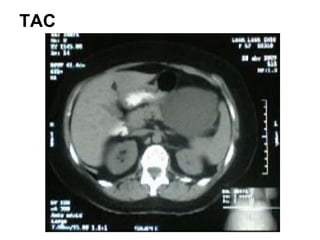

How to have difficult conversations Caso Quiste de Pancreas: Imagenes